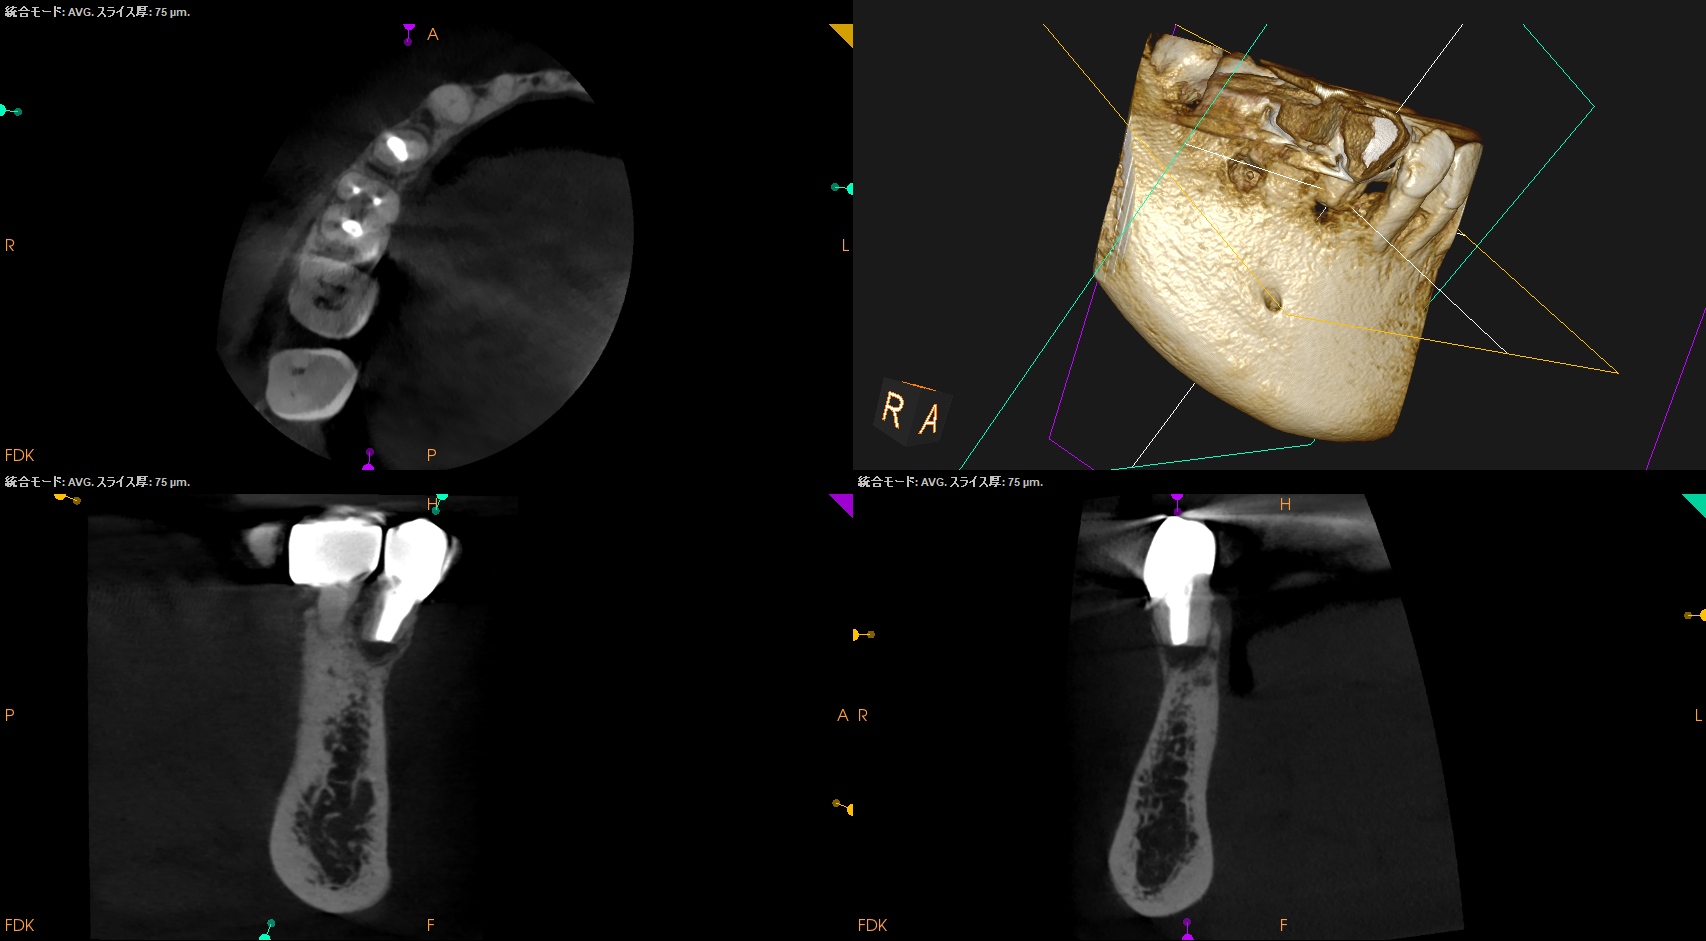

#29 Intentional Replantation 2M recall(2026.1.9)

PA, CBCTを撮影した。

歯槽骨は順調に回復している。

破折しているわけではなかったのだ。